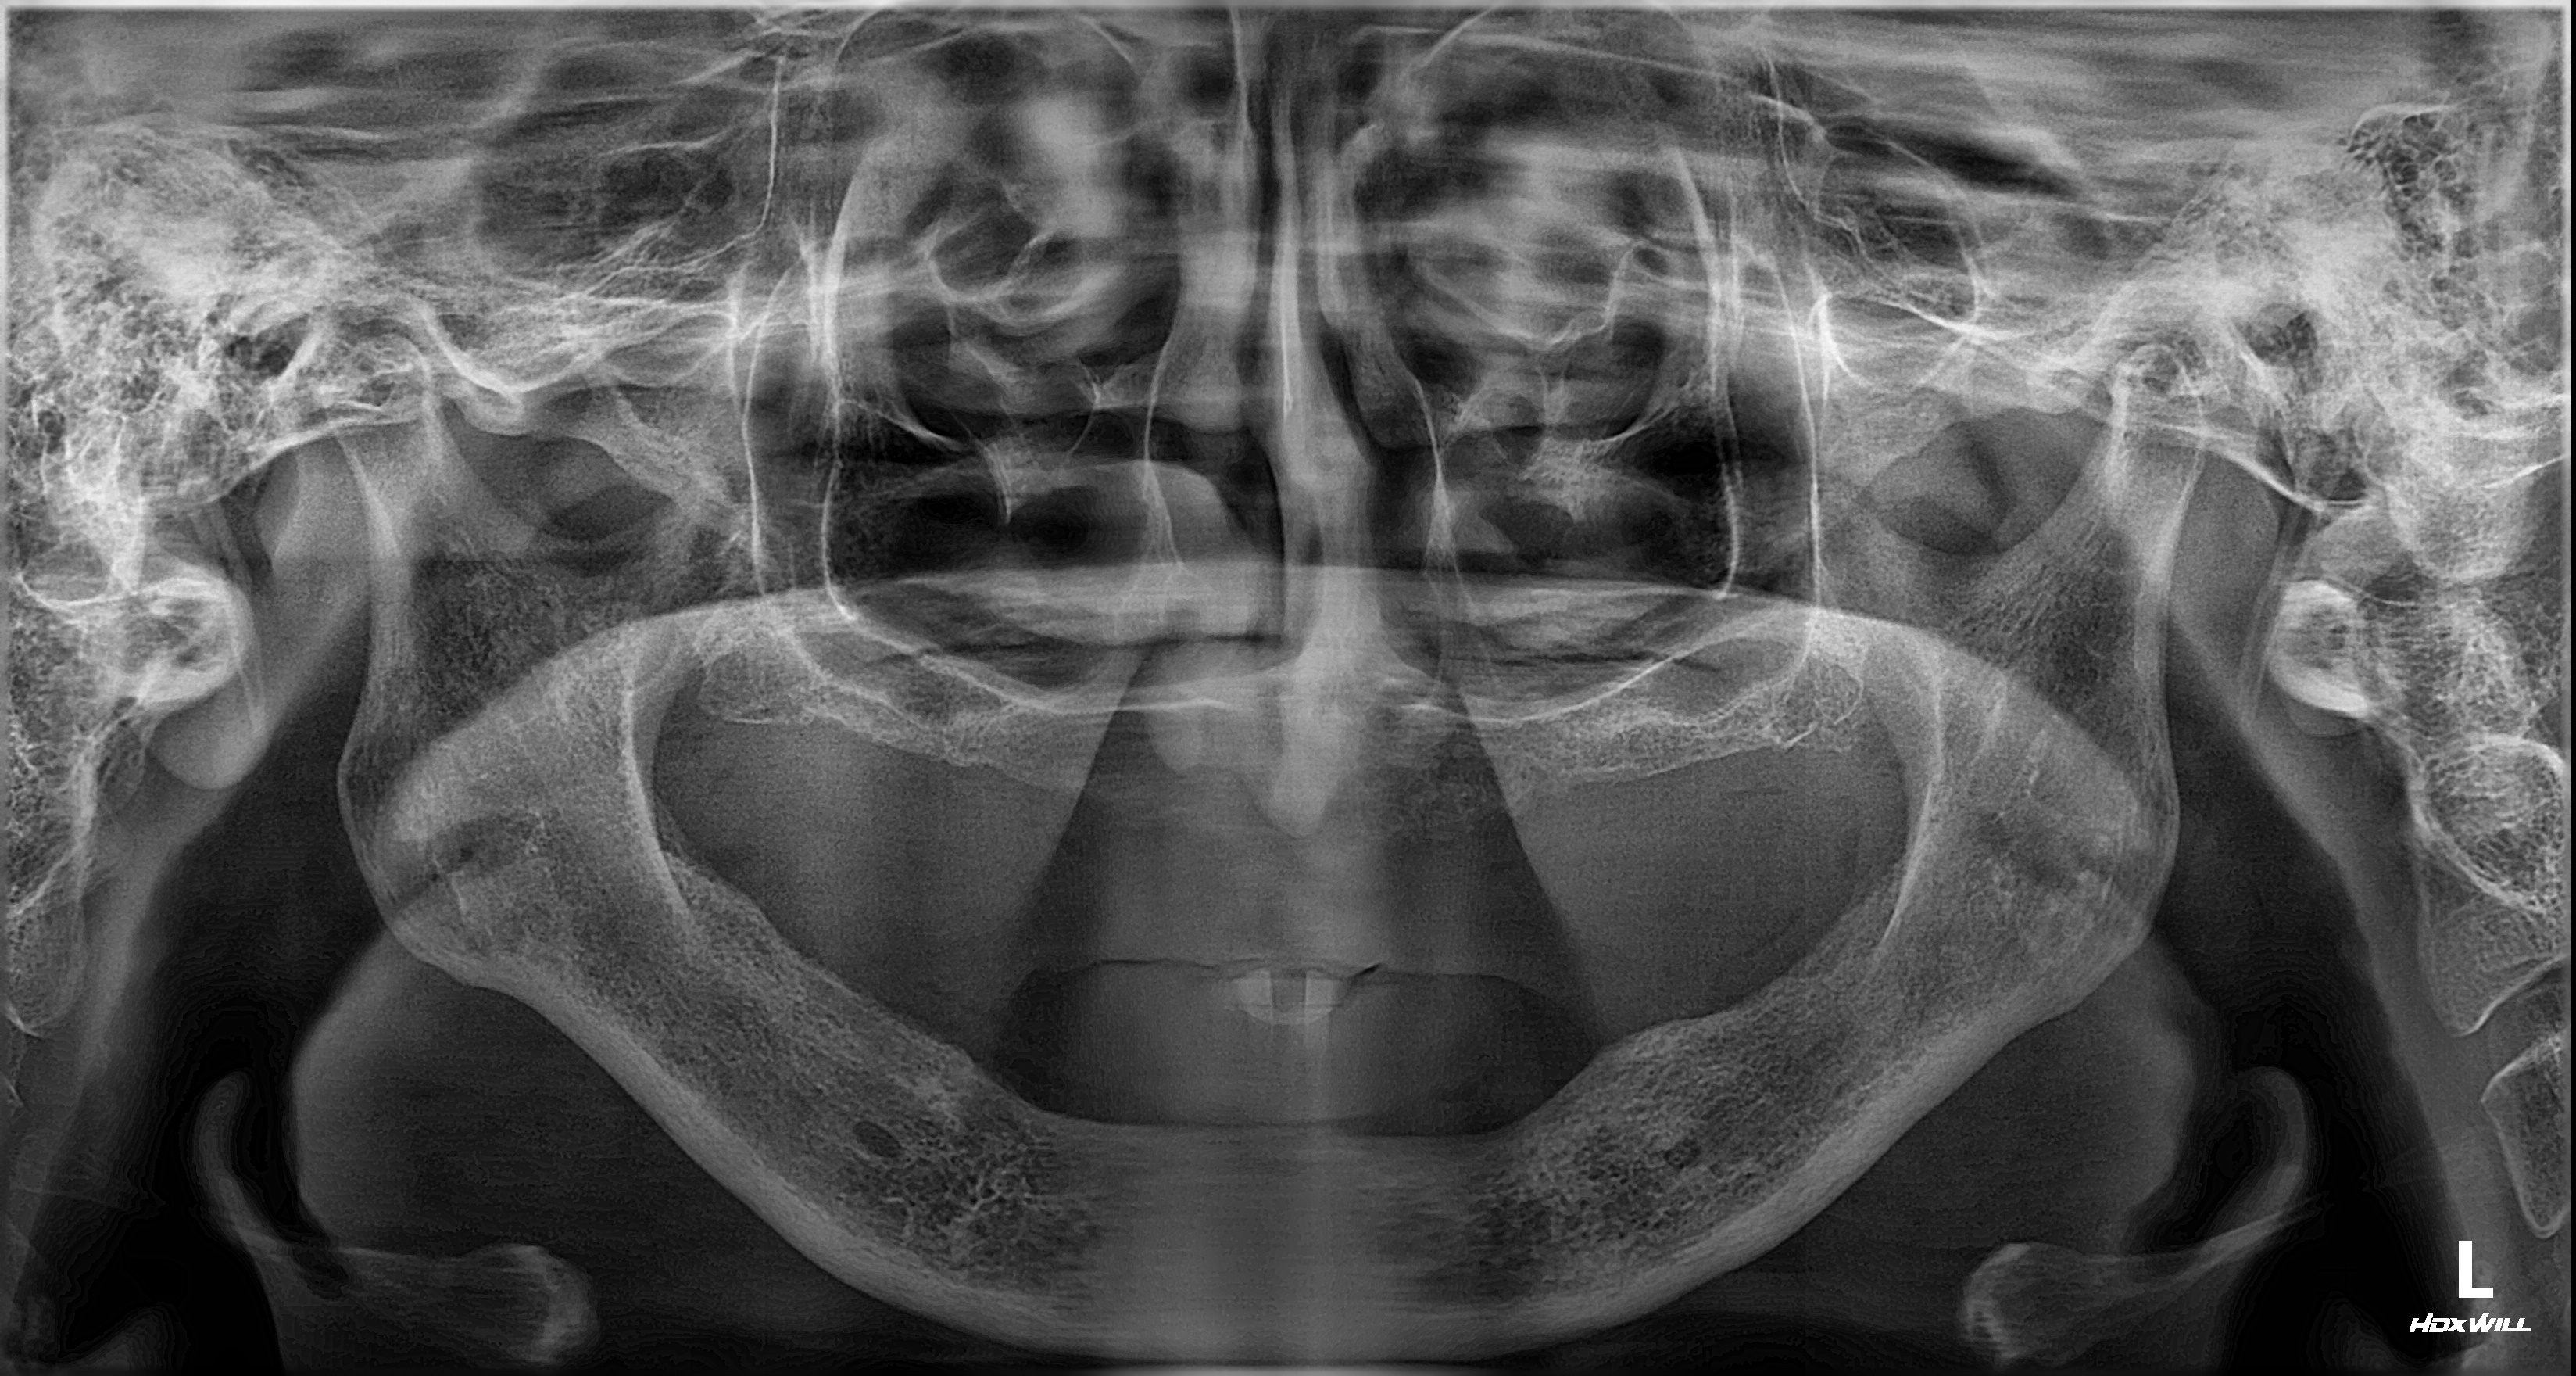

촬영일시: 2025.03.20.